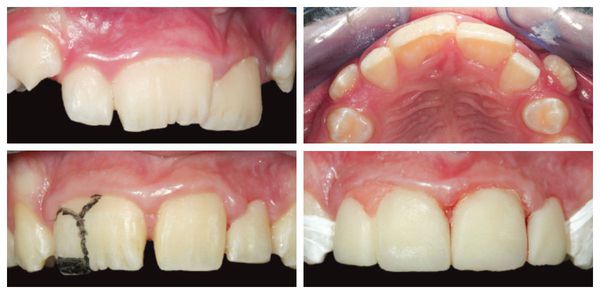

Przy mikrodoncji (microdontia) sytuacja jest odwrotna — zęby (pojedyncze lub kilka) są mniejsze niż norma, co skutkuje powstawaniem przerw między nimi (szpar, diastem). Zęby mogą mieć również stożkowaty kształt, a nadmierne odstępy wpływają na estetykę uśmiechu, fonetykę oraz prawidłowe rozłożenie sił żucia.

Makrodoncja (po lewej) i mikrodoncja (po prawej)

Leczenie mikrodoncji (mikrodoncja, zbyt małe zęby) polega na połączeniu terapii ortodontycznej z kompleksową rehabilitacją protetyczną, której celem jest poprawa estetyki uśmiechu i przywrócenie prawidłowej funkcji zgryzu.

Etap ortodontyczny obejmuje:

• przemieszczanie zębów (przesuwanie zębów) w celu ich wyrównania i korekcji ustawienia;

• zamykanie przerw między zębami (diastemy, tremy), które często towarzyszą mikrodoncji;

• stworzenie miejsca w łuku zębowym pod przyszłe odbudowy protetyczne.

Po zakończeniu leczenia ortodontycznego następuje etap rekonstrukcji estetycznej, który może obejmować:

• odbudowę zębów materiałem kompozytowym,

• pokrycie zębów licówkami (licówki, veneers),

• założenie koron protetycznych (korony) – gdy konieczna jest pełna korekta kształtu i wysokości zęba.

Dzięki temu zęby uzyskują prawidłowe proporcje, naturalny kształt i kolor, a pacjent odzyskuje estetyczny uśmiech oraz prawidłową funkcję żucia.

Odbudowa zęba stożkowatego